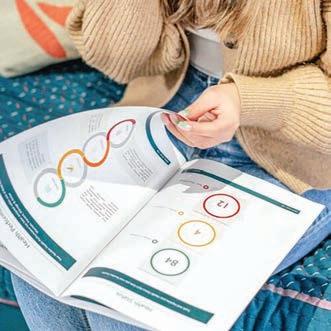

The results speak for themselves. After a 12-week independent clinical trial, 84% of participants noticed increased immunity and emotional balance, 92% noticed significant improvements in the condition of skin, hair and nails, while 84% felt improved energy. And while most users see the benefits within weeks, Lumity recommends a minimum commitment of 12 weeks to see the best results. With continued use, these benefits are sustained, resulting in overall improved energy levels, more youthful skin, a stronger immune system and a new, happier balance.

Our popular Everyman/Everywoman health programme includes two full health checks six months apart to help you track and improve your health data. Up to 150 data points linked to key health areas are measured during each visit. A personalised health plan summarising your results is then provided, as well as a follow-up consultation with a scientific expert.

Our elite Signature health package has been curated to focus on your full-body wellbeing with a specific emphasis on areas of your health that are important to you. Included within the package are two full health checks six months apart, measurement of up to 350 data points including tumour markers and digestive health, three private GP consultations,

access to genetic testing, an ECG, bowel health at home test, biometric analysis and private prescriptions/referrals if required.